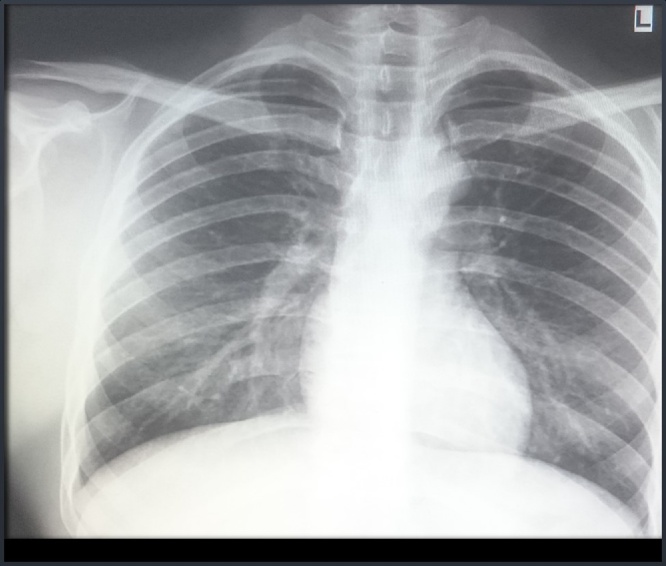

A 27-year-old male came to our hospital with complaints of a swelling in the right axilla for 2 and ½ years. It was insidious in onset and progressive in nature. The patient denied any history of pain, trauma, fever or weight loss. On examination, the swelling measured 12 cm × 10 cm, extending to the lateral border of the right scapula posteriorly, to the chest wall medially, to the apex of the axilla superiorly and to the 6th intercostal space inferiorly (Fig. 1). There was no warmth or tenderness noted. Skin over the swelling was normal and the surface was nodular. Dilated blood vessels were present over the surface of the swelling (Fig. 2). There were no visible pulsations, no discharge and no scars or sinuses. Movement of the shoulder joint was normal. The swelling was hard in consistency and not mobile. There were no palpable axillary or cervical lymph nodes. Baseline blood investigations were normal. Chest X-ray was normal and showed no osteolytic lesions of the right ribs or scapula (Fig. 3). Magnetic Resonance Imaging was done and showed an irregular mass in the right axilla in the muscular- subcutaneous plane measuring 10.8 × 8.8 × 12 cm. This mass was attached to the lateral border of scapula (Fig. 4) and displaced the subscapularis anteriorly. The infraspinatus, teres minor and teres major muscles were displaced posteriorly (Fig. 5). The lesion appeared iso to hyperintense to muscle on T1 and heterogeneously hyperintense on T2-weighted images. Multiple scattered areas of hemorrhage were noted within. The neurovascular bundle was seen displaced cranially. The lesion abutted the median, radial, ulnar nerves and axillary vessels in few sections. The lesion abutted the serratus anterior on the medial aspect.

Fig. 3.

Chest X-Ray showing no osteolytic lesions.